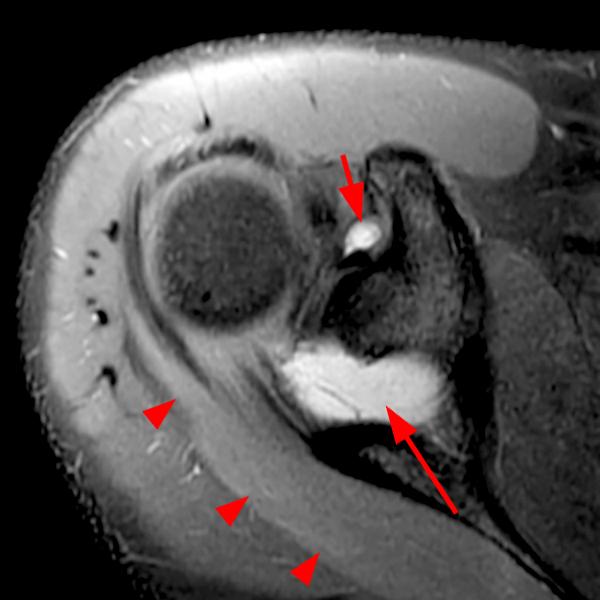

Shoulder Cysts Mri

From mavink.com

Shoulder Cysts Mri Back Shoulder Cyst A paralabral cyst, or ganglion cyst, is a fluid collection arising from the shoulder’s ball and socket joint. Let’s start by looking at the four most common causes of a lump on the back of your shoulder and how to treat them. A sebaceous cyst on the shoulder, aka epidermoid shoulder cyst is a small sac filled with keratin, a. Back Shoulder Cyst.